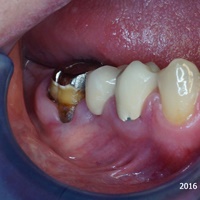

Pod koroną w moście rozwinął się proces zapalny obejmujący fiurkację dalszą zęba 26. Po radektomi wykonano nowy most, na tych samych zębach filar.